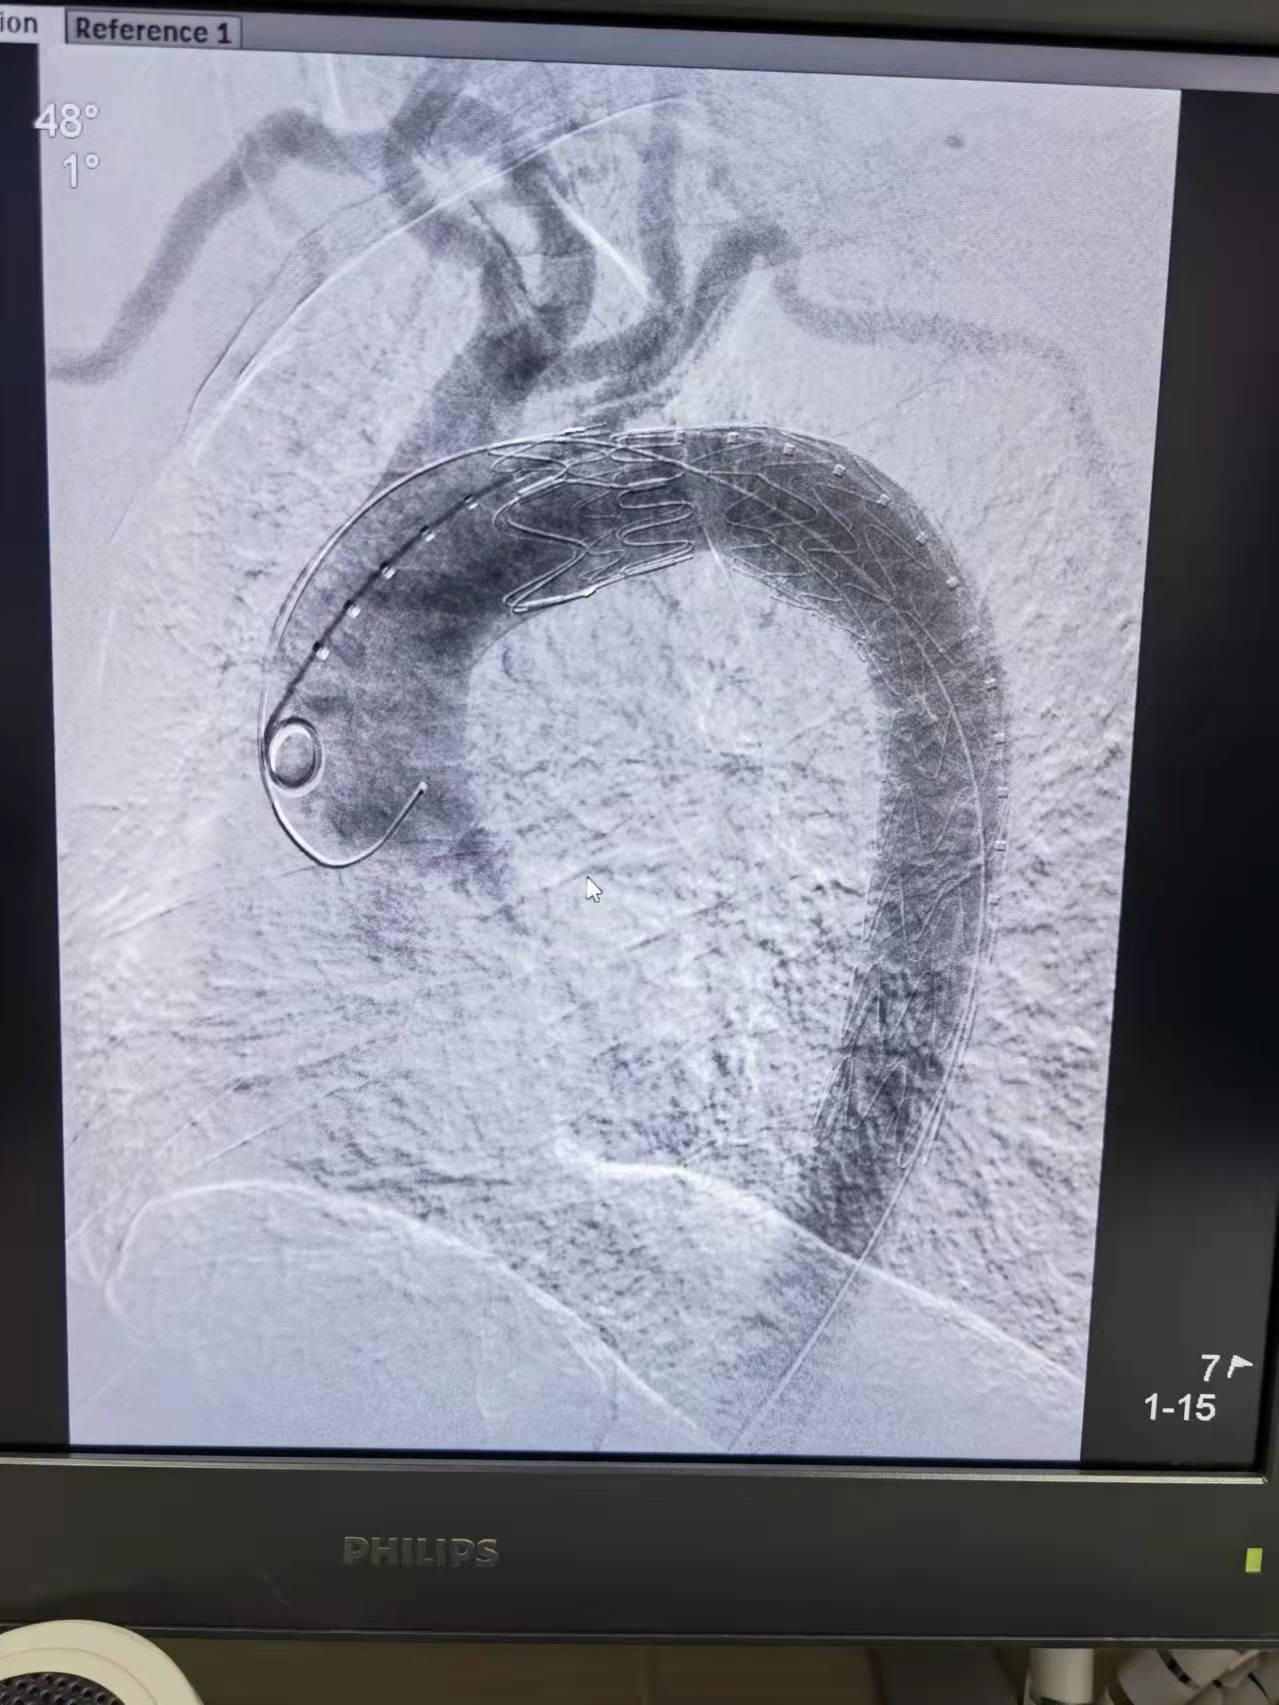

一切准备就绪后,手术按计划顺利进行,由于秦大爷的溃疡病变位于近头部供血血管附近(左锁骨下动脉),选择同时行胸主动脉支架“预开窗”技术来保留左锁骨下动脉,手术采用单纯穿刺股动脉完成,穿刺口仅仅1cm左右,避免了腹股沟切开减少了他的创伤,也节省了手术时间,2小时后手术顺利结束,秦大爷全程清醒,并没有感觉到任何疼痛。